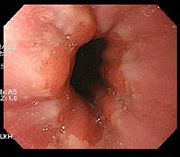

사례 1

치료 후 치료 후 장내 점막 회복 사진